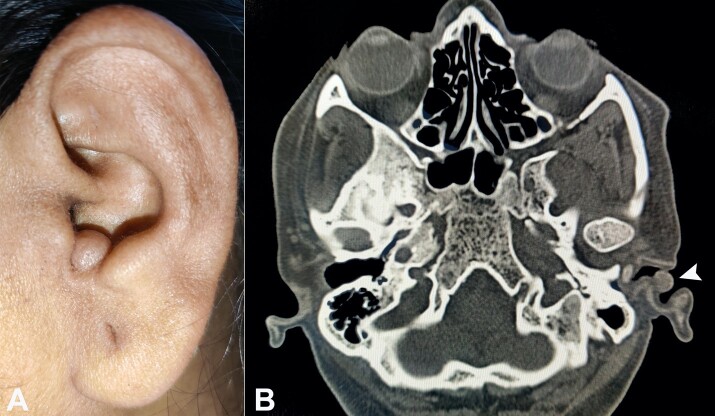

外耳道圆筒状瘤是一种罕见的肿瘤,主要表现为位于耳道外侧的无痛肿块。它们在文献中被指定为不同的命名,关于其病因和组织发生的争议持续存在。此外,EAC圆筒状瘤的临床诊断往往具有挑战性,因为其罕见且与其他附件良性和恶性肿瘤非常相似。以前的作者都没有广泛地回顾过EAC的真皮柱状瘤。我们提供包括PubMed和Google Scholar在内的广泛评论,并根据系统评论和元分析标准的首选报告项目进行报告。本研究共纳入8例。平均年龄55.13岁。有六名女性和两名男性。累及左耳和右耳的比例分别为62.50%和37.50%。最常见的体征/症状是无痛性肿块(50%)。5位作者报告原发病变(62.50%),其余3位报告复发肿瘤(37.50%)。良性和恶性圆柱状瘤分别占87.50%和12.50%。除一例外,所有病例均报告为单发肿胀。所有病例均行手术切除。原发性缺损闭合与局部/远处皮肤移植/皮瓣闭合的比例分别为37.50%和62.50%。

External auditory canal (EAC) cylindroma is a rare tumor that mainly presents as a painless mass over the lateral aspect of the ear canal. They have been designated under different nomenclatures in the literature, and controversies persist about their etiology and histogenesis. Moreover, a clinical diagnosis of EAC cylindroma is often challenging because of their rarity and a close resemblance with other adnexal benign and malignant tumors. None of the previous authors have extensively reviewed the dermal cylindroma of the EAC. We provide an extensive review involving PubMed and Google Scholar and report by Preferred Reporting Items for Systematic Reviews and Meta-Analyses standards. A total of 8 cases are included in the current study. The mean age is 55.13 years. There are six females and two males. The left and right ear are involved in 62.50% and 37.50% of cases, respectively. The most common sign/symptom is painless mass (50%). Five authors reported a primary lesion (62.50%), while the remaining 3 reported a recurrent tumor (37.50%). Benign versus malignant cylindroma is reported in 87.50% and 12.50% of cases, respectively. All, except one case, reported a solitary swelling. Surgical excision was employed in all the cases. Primary defect closure versus defect closure with local/distant skin graft /flap is utilized in 37.50% and 62.50% of cases, respectively.